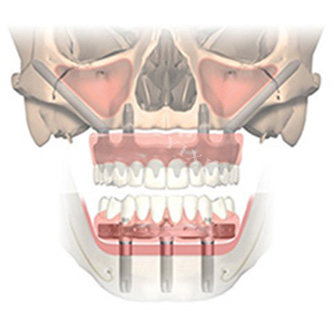

种植牙手术是通过外科手术的方式将人工牙根(种植体)植入缺牙部位的牙槽骨内,经过一段时间(通常为 3 - 6 个月),使种植体与牙槽骨形成牢固的骨结合,然后安装基台、牙冠,从而改善牙齿的形态和功能。在开封河川口腔,经验充足的医生会在术前通过口腔 CT 等新型设备,对患者的口腔状况进行齐全评估,制定个性化的种植方案。

手术时,医生会先对患者进行局部麻醉,以确保在手术过程中患者不会感到明显疼痛。在麻醉起效后,医生切开牙龈,暴露牙槽骨,使用正规工具在牙槽骨上制备种植窝,将种植体植入其中,缝合创口。整个过程中,新型的医疗设备和精细的操作技术,能大程度减少对周围组织的损伤,降低患者的不适。